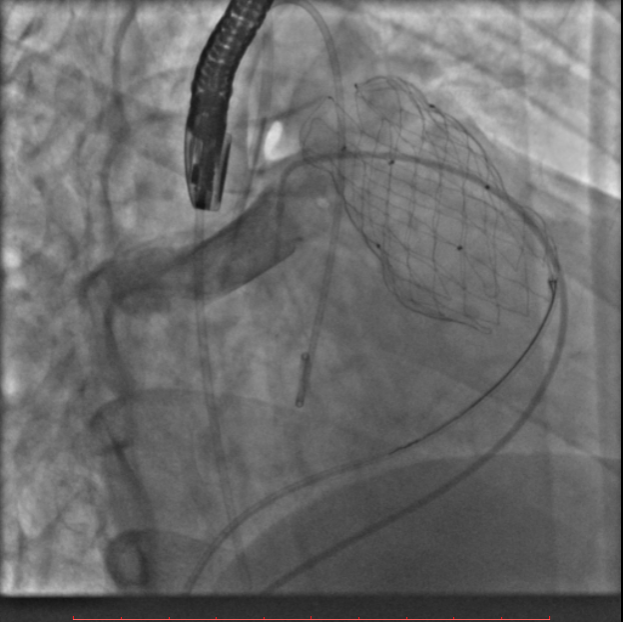

术前通过肺动脉CTA评估患者肺动脉瓣环直径为32mm、肺动脉分叉处直径为35mm、主肺动脉长度为23mm(见图一)。

图一:肺动脉瓣环直径32mm,肺动脉分叉处直径35mm,主肺动脉长度23mm